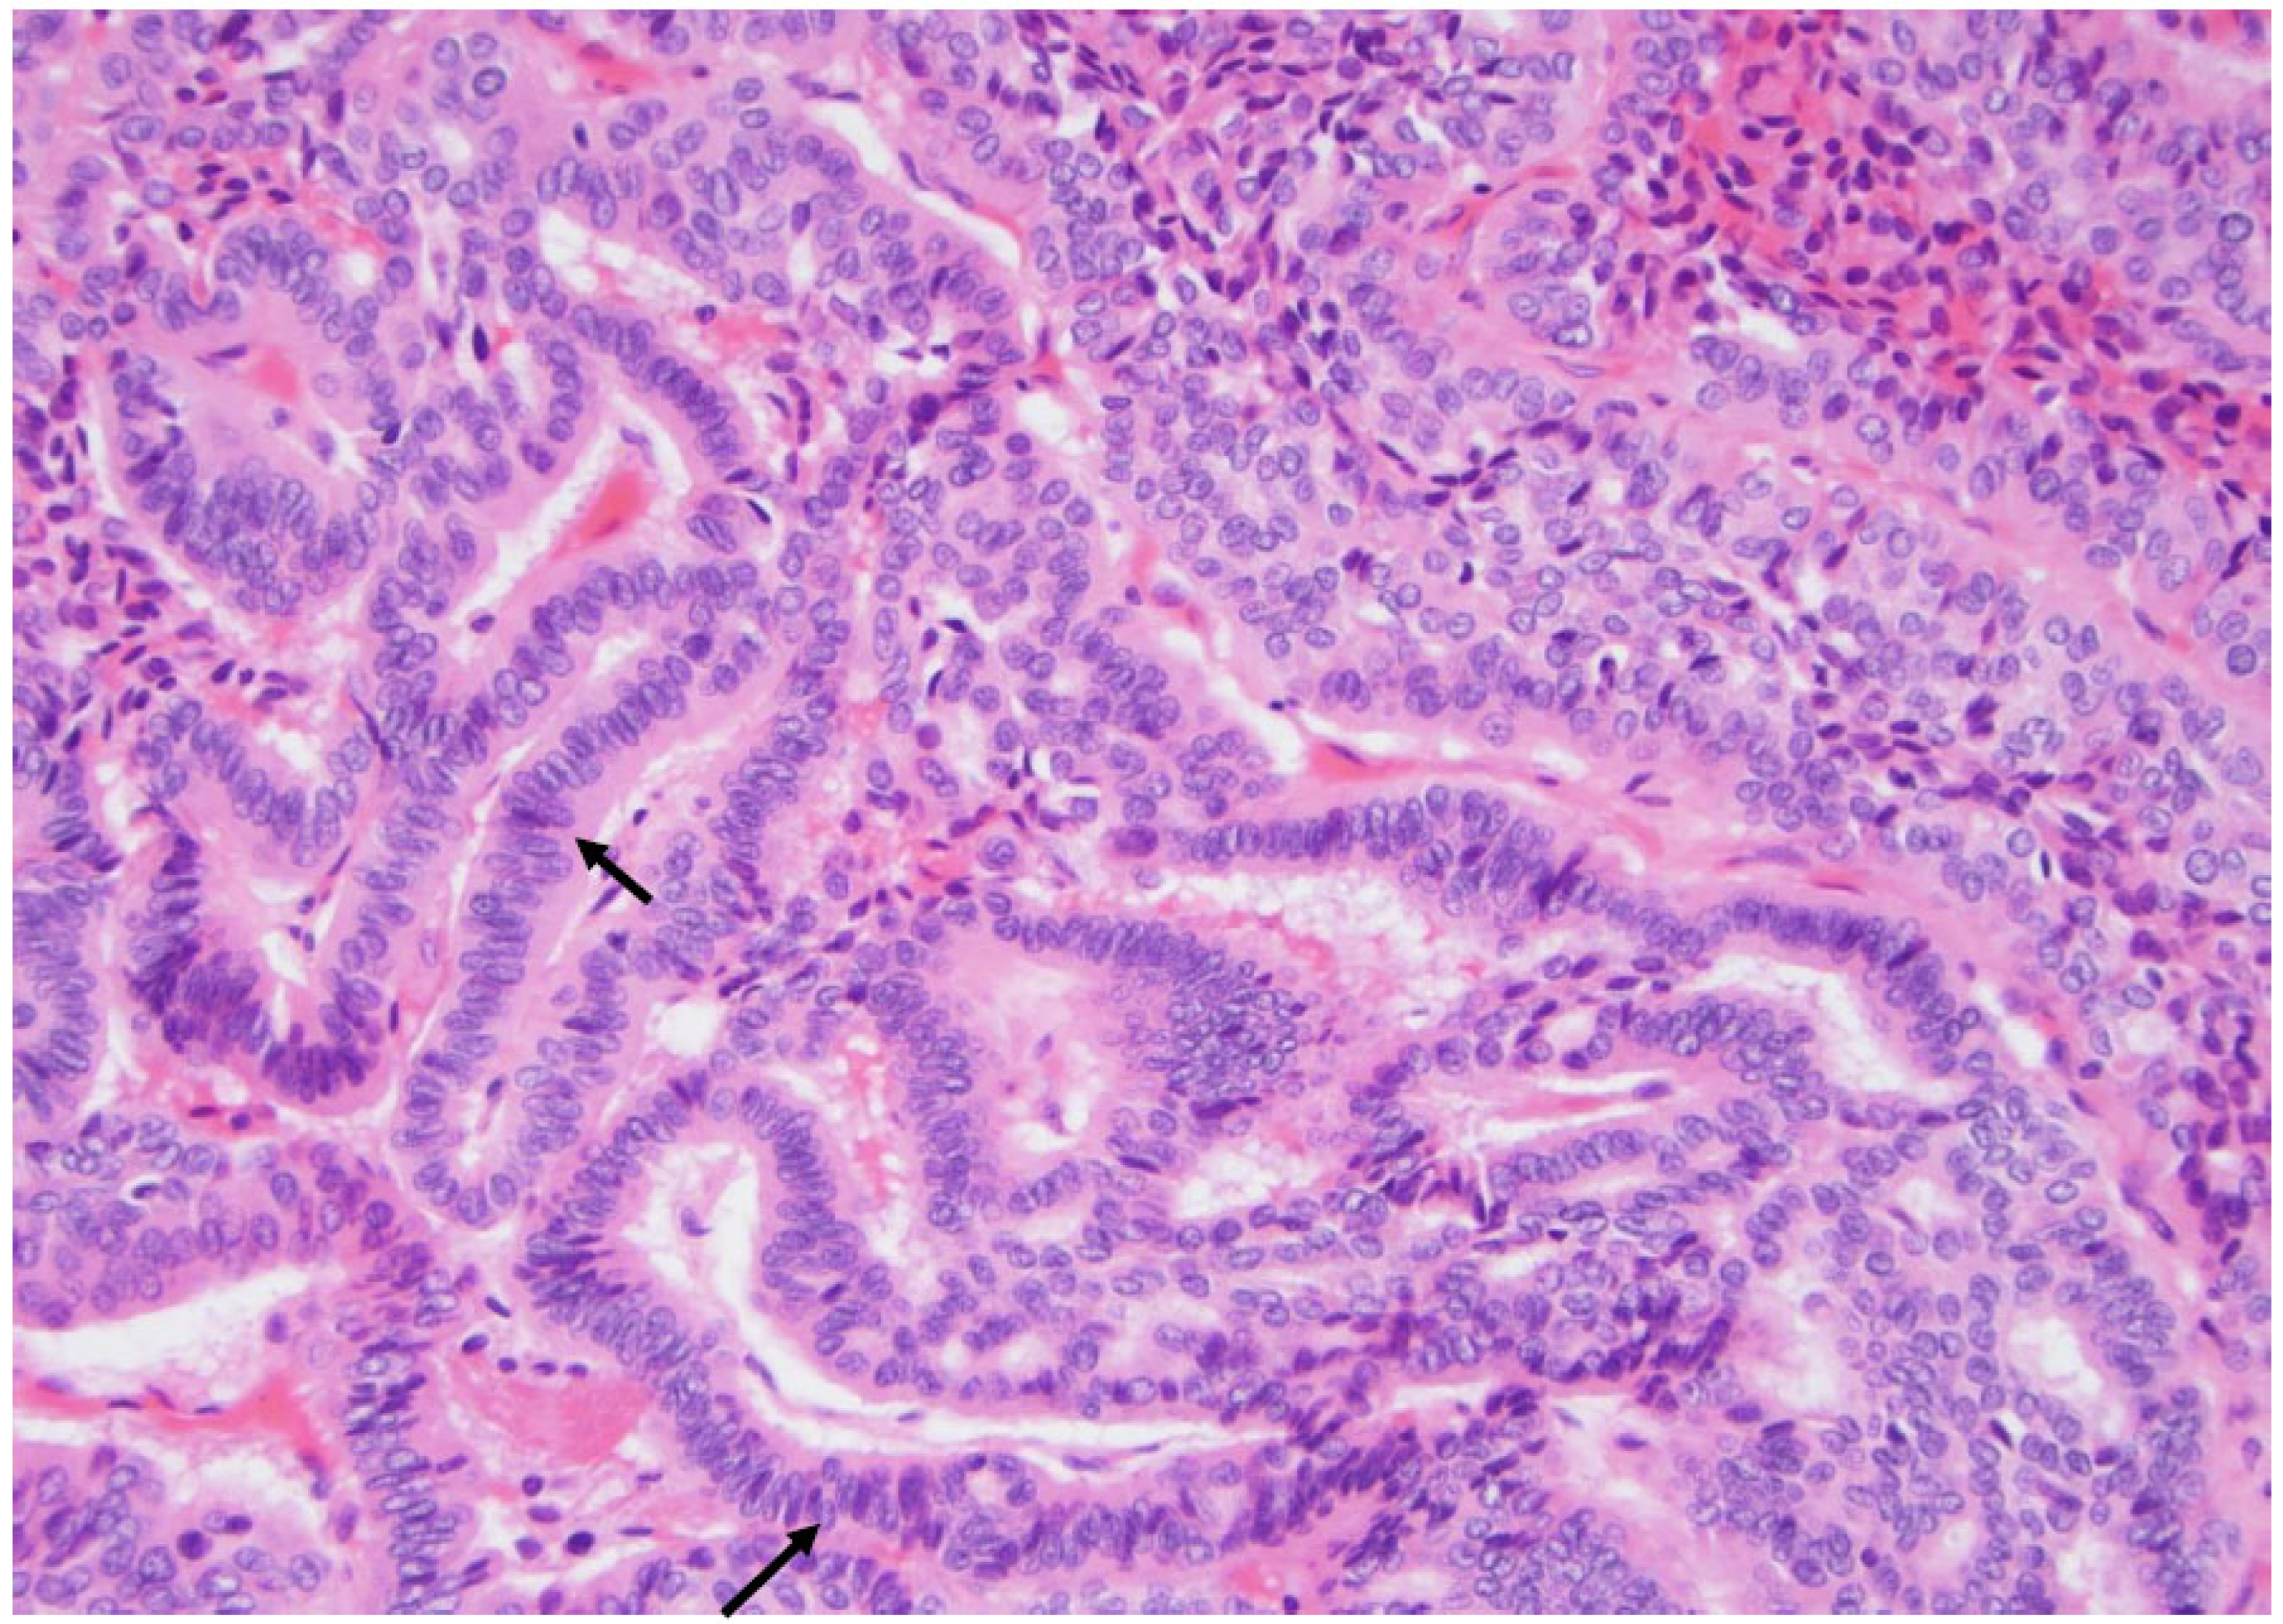

Figure 2. The classic type of papillary carcinoma is entirely composed of papillary structures, i.e., a central fibrous core lined by atypical cells (arrow), as seen here (×200, H&E stain).